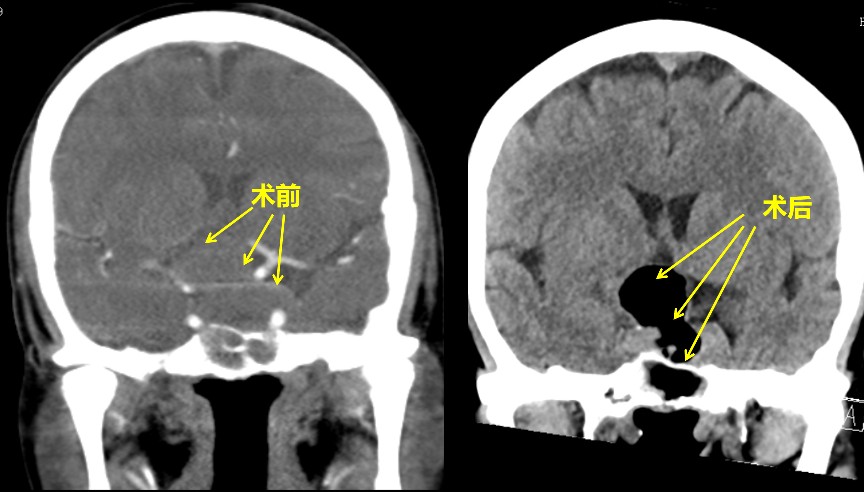

经过科室讨论和院内多学科会诊,并与患者及家属充分沟通后,患者家属决定选择在鼻内镜下微创行经鼻垂体瘤切除术,我们在术中采取双人三手、双人四手操作,密切配合,完整切除肿瘤,并保护了鞍膈的完整性,双侧颈内动脉也未受损,术中出血约350ml,未出现脑脊液漏,未输血。术后鼻腔填塞少量止血材料,患者无明显头痛等不适,术后第一天,左眼视力即由原来的只能感觉眼前的手动,升为可以辨别眼前的手指个数了,提示明显改善。术后尿量在正常范围,未出现尿崩(垂体瘤术后常见的并发症之一)。术后复查CT提示,垂体肿瘤切除干净。患者术后一周即出院了。

患者术后7月来院复查,左眼视力已恢复到0.8,而且已在外地打工,恢复了劳动力。患者的嗅觉功能也正常。在很多垂体瘤术后的患者中,往往抱怨术后嗅觉有下降,严重者甚至嗅觉丧失,这是由于手术过程中可能有些术者为了手术通道,切除了与嗅觉相关的上鼻甲及鼻中隔后部分嗅区结构和组织,文献报道术后嗅觉障碍的发生率还是比较高的。在这例患者中,我们采取了改良的手术径路,很好地保护了上鼻甲和鼻中隔嗅区黏膜,术后的嗅觉功能得以完好地保存,这对患者术后生活质量的改善也是很重要的。